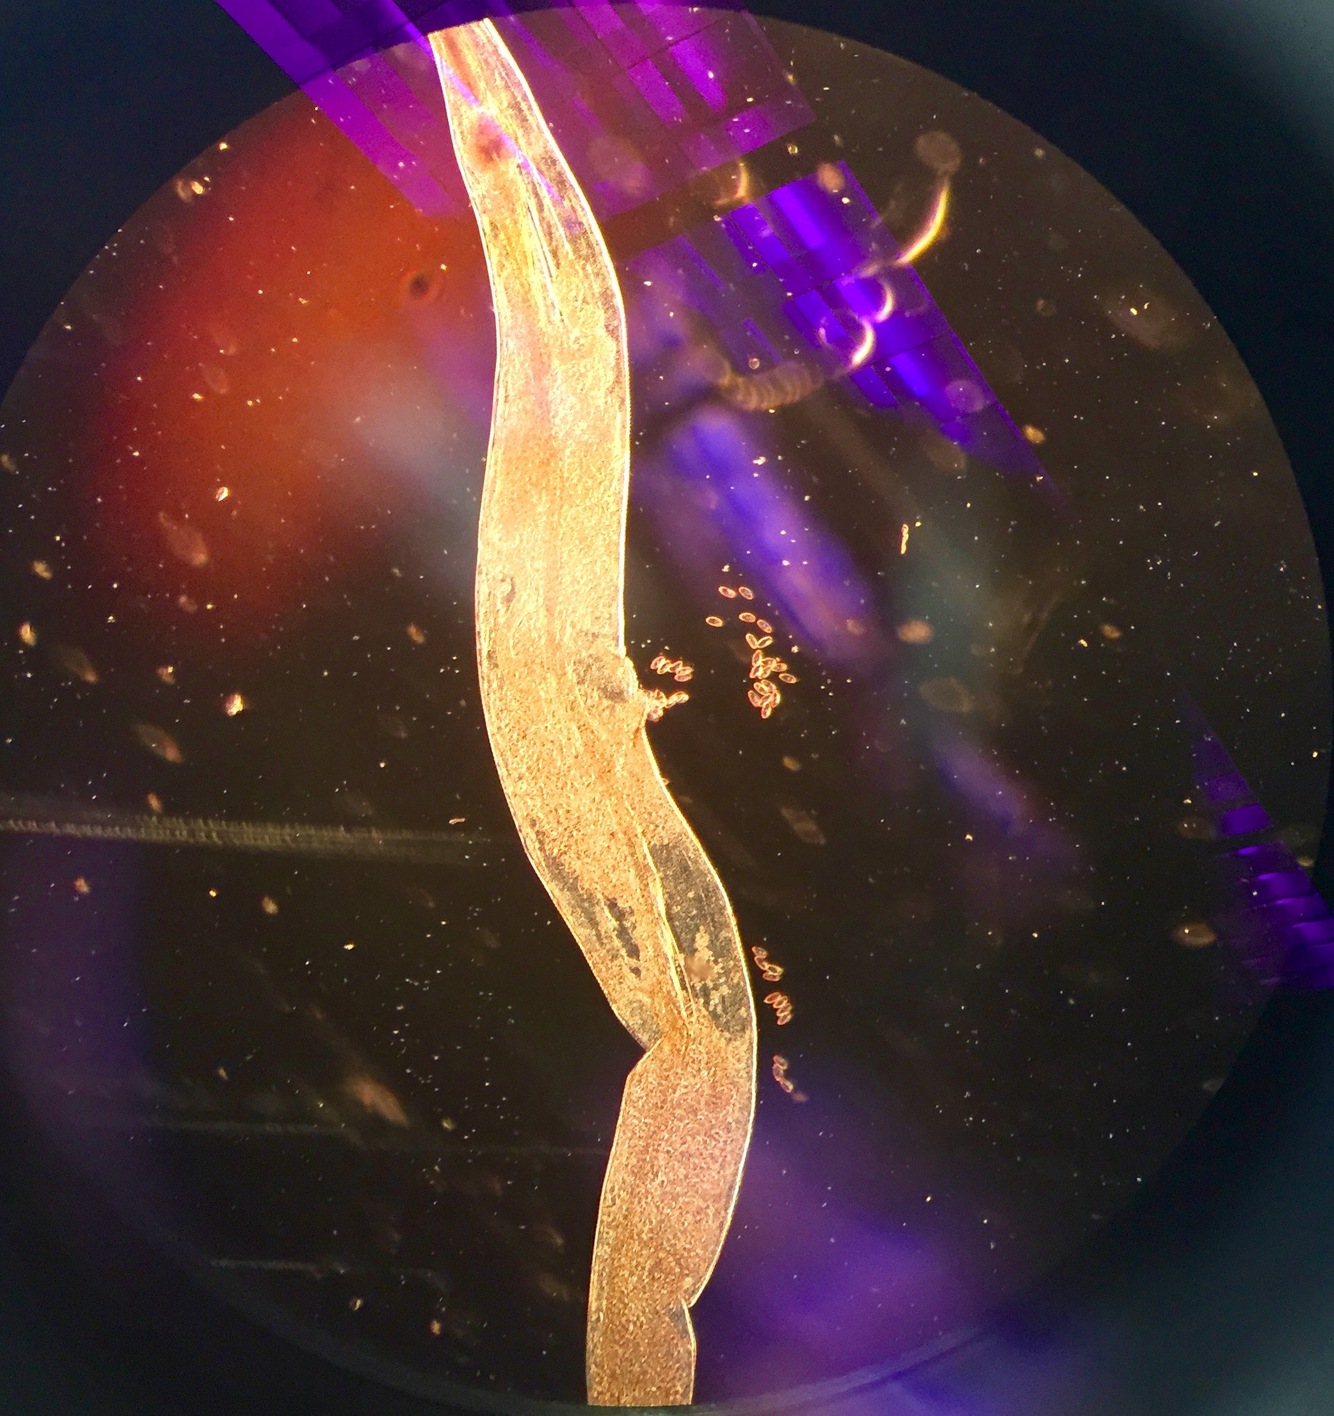

Kingdom?

Phylum?

Genus species?

Infected by?

Host?

Symptoms?

Animalae

Nematoda/round worm

Trichinella spiralis

Infected by- Ingestion of undercooked meat

Host- carnivorous mammals

Symptoms? Muscle pain